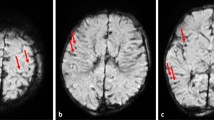

The 7 T T2 images presented higher contrast between the different structures of the brain tissue than the 3 T T2 images (Fig. 3a/d). The 7 T T2-SPACE sequence enabled a precise depiction of soft tissue injuries beyond the wound tract and a detailed depiction of anatomical structures. Cavitation injuries were detected beyond the wound tract, although identification of bone fragments and gas was challenging on MRI (Fig. 4). The wound tract through the collapsed brain tissue was more difficult to identify on 3 T than on 7 T (Fig. 5). Several microbleeds were visible only on 7 T MRI (Fig. 6). The Likert scale grades of T2-weighted images (Table 1) were significantly higher (p = 0.030) on 7 T MRI than on 3 T MRI.

Comparison of 7 T T2-weighted images (a: sagittal view; c and e: transversal view) and 3 T T2-weighted images (b: sagittal view; d and f: transversal view) in case 3. The wound tract is identifiable on 7 T MRI (a: arrows) but difficult to delineate on 3 T MRI (b: arrows). In a cross-section of the bullet path (c and d: aligned according to the white arrows in a and b; e and f: aligned according to the white dashed arrow in a and b), 7 T allowed visualization of tiny injuries along the bullet path (c: white circle, hyper intense/dark structures) that were barely identifiable on 3 T (d: white circle). Furthermore, the tiny wound tract through the white matter was visible only on 7 T MRI (e: arrowhead 1). A small bright/hyper intense region was identified directly adjacent to the wound tract (arrowhead 2)